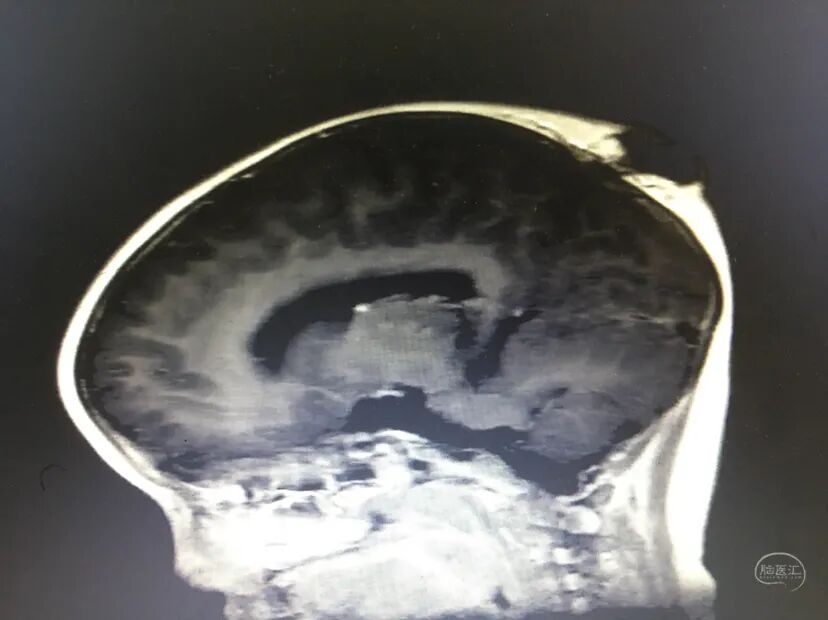

病例情况

术前情况